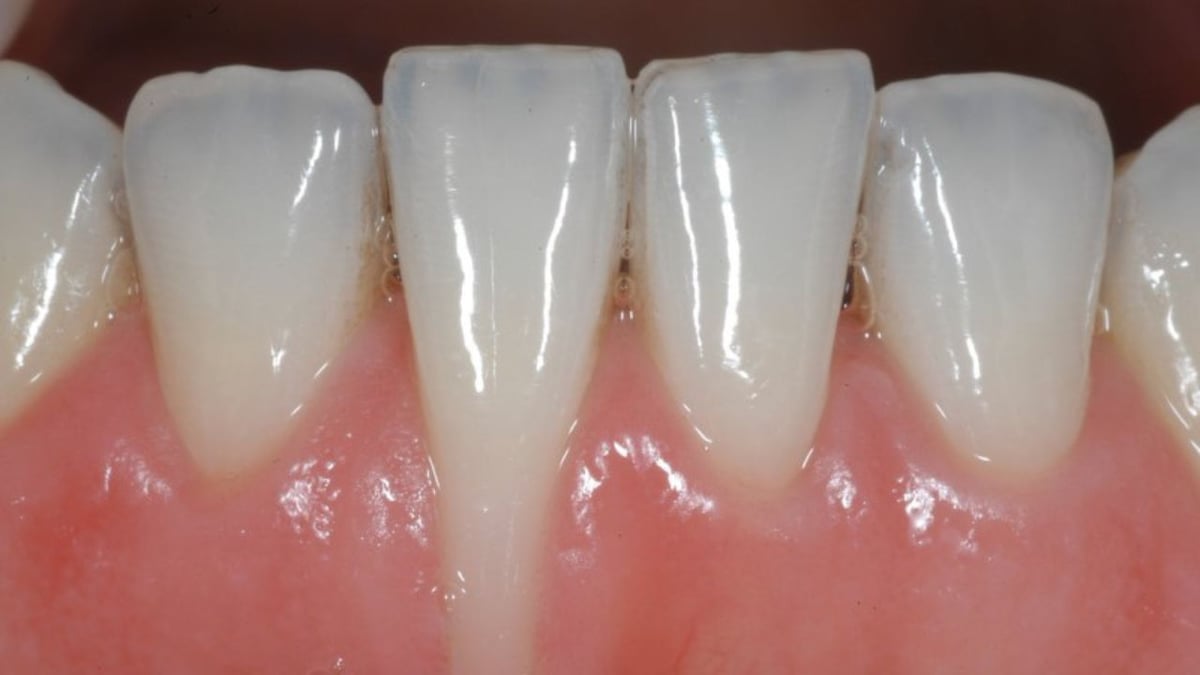

Sưng nướu trong cùng hàm dưới: Nguyên nhân và cách điều trị

Sưng nướu trong cùng hàm dưới là một vấn đề răng miệng phổ biến nhưng thường bị bỏ qua cho đến khi triệu chứng trở nên nghiêm trọng. Tình trạng này không chỉ gây khó chịu và đau đớn mà còn có thể dẫn đến những biến chứng nghiêm trọng hơn nếu không được điều […]